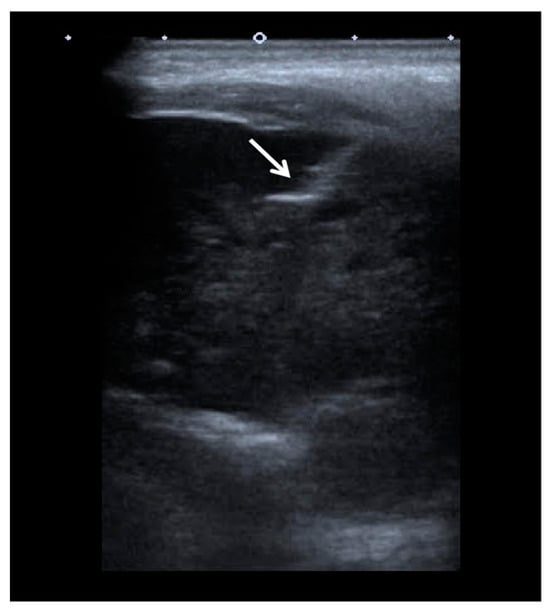

2. Case Report